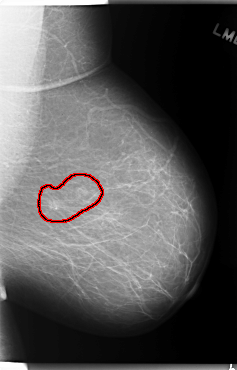

C_0132_1.LEFT_MLO

LEFT_MLO LINES 5920 PIXELS_PER_LINE 3784 BITS_PER_PIXEL 12 RESOLUTION 50 OVERLAY

FILE: C_0132_1.LEFT_MLO.OVERLAY

TOTAL_ABNORMALITIES 1

ABNORMALITY 1

LESION_TYPE CALCIFICATION TYPE PLEOMORPHIC DISTRIBUTION CLUSTERED

LESION_TYPE MASS SHAPE OVAL MARGINS ILL_DEFINED

ASSESSMENT 4

SUBTLETY 4

PATHOLOGY MALIGNANT

TOTAL_OUTLINES 1

BOUNDARY